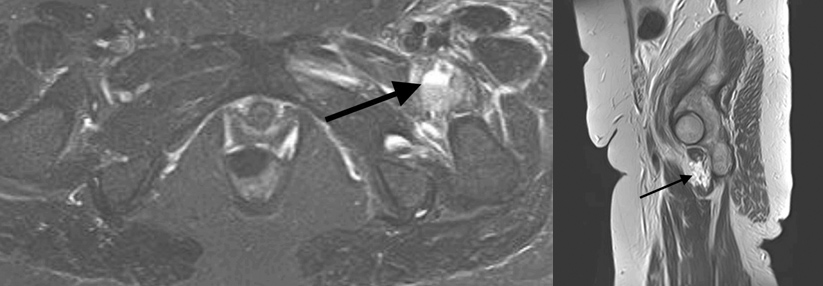

Röntgenologisch zeigt sich im Sitzbein eine tumoröse Auftreibung mit angedeuteter Periostreaktion (Abb. 1). Im Kontrastmittel-MRT stellt sich im Os ischii eine hypodense Läsion dar (Abb. 2). Das postoperative MRT ergibt keine Hinweise auf ein Rezidiv (Abb. 3). Röntgenologisch zeigt sich im Sitzbein eine tumoröse Auftreibung mit angedeuteter Periostreaktion (Abb. 1). Im Kontrastmittel-MRT stellt sich im Os ischii eine hypodense Läsion dar (Abb. 2). Das postoperative MRT ergibt keine Hinweise auf ein Rezidiv (Abb. 3). © Gulbins H, Johann M. Wehrmedizinische Monatsschrift 2020; 64: 218-220 © Beta Verlag & Marketinggesellschaft mbH, Bonn